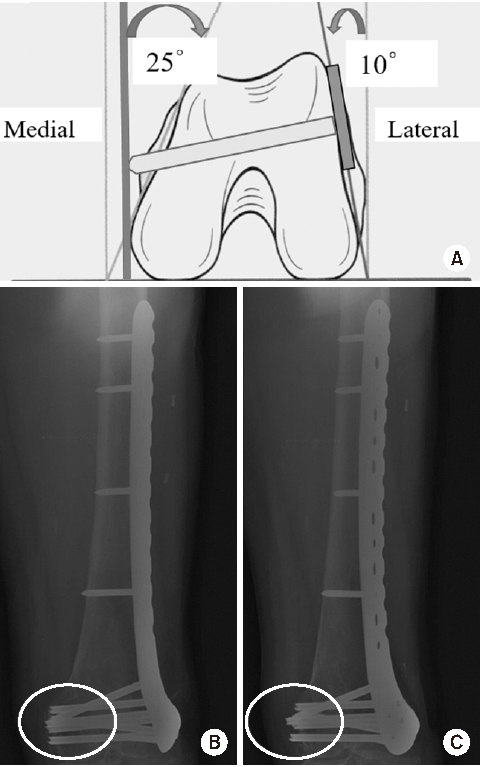

Fig. 3

Appropriate plate length and plate-screw density after minimally invasive plate osteosynthesis using a locking plate in osteoporotic distal femur fractures.